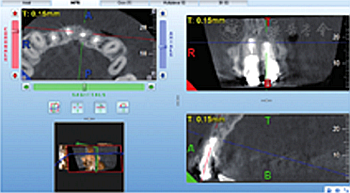

见图8,图9,图10,图11。分别于术后3、6个月时复查根尖X线片,8个月时复查锥形束CT并分别进行临床检查。复查结果显示根尖病变已愈合,根尖无明显低密度影。临床检查叩诊正常,无松动,牙龈位置无明显变化。

图11 术后8个月复查锥形束CT截面显示患者根尖病变已愈合